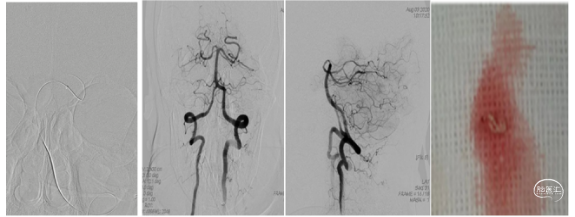

右侧颈总造影发现,右侧颈内动脉起始处有斑块,两处充盈缺损。

使用泥鳅导丝试探,很幸运,毫不费劲就通过了狭窄处,因此考虑此处未完全闭塞,而且远处的栓子可能就来源于此处。将5F125cm Navien沿着泥鳅导丝轻松通过狭窄处,进行抽吸清理颈内动脉可能滞留血栓。跟进8F导引导管通过狭窄部位起到支撑作用。

上干和大脑前为功能区血管,应该开通:

先开通大脑中M2段。支架导管到位,确认远端通畅,尼科医疗的Reco支架3X20mm到位,5F Navien跟到M1,一边抽吸一边拉栓,一把拉通。

注意:应该微导管半收拢支架钳夹血栓,缓慢回拉,防止牵拉血管支撑组织导致脑出血。

再开通大脑前A2段,同样尼科医疗的Reco支架3X20mm到位,5F Navien 跟进A1,半收拢支架,一边抽吸一边拉栓,一把拉通。

回头处理颈内动脉起始部。常规保护伞4-6mm保护下行4-6mm球囊扩张,并自膨支架7-9-40mm植入。